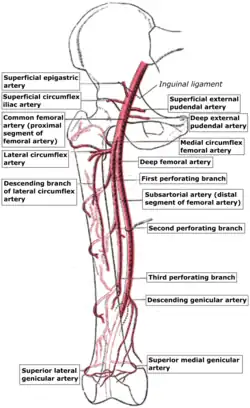

Scheme of the femoral artery. (Superficial external pudendal artery labeled at upper right.) | |

The femoral vein and its tributaries. Schema of the arteries arising from the external iliac and femoral arteries.

Schema of the arteries arising from the external iliac and femoral arteries. Anterior abdominal wall.Intermediate dissection.Anterior view